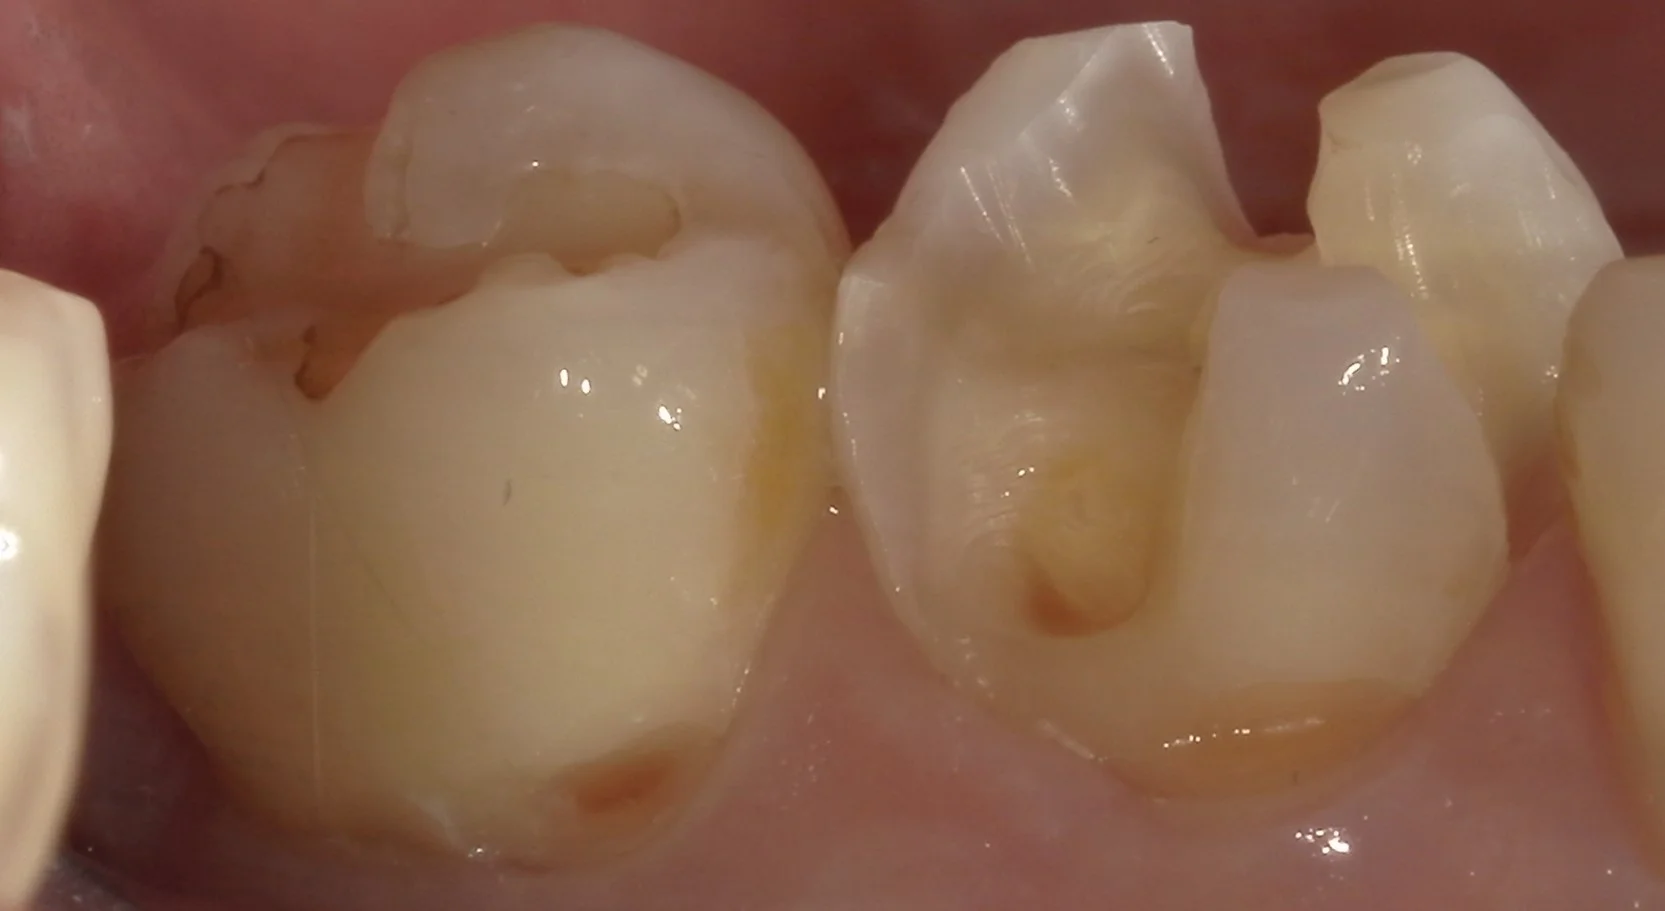

まずは術前の噛む面からの写真です。

続いて、側面からの写真です。

非常に広範囲に金属の詰め物が詰められているのが分かるかと思います。

また、歯茎の際辺りが歯ブラシの圧で抉れてしまっています。

こういった状態を「楔状欠損」と言い、実はダイレクトボンディングの中で治療が最も難しいと言われている状態になります。